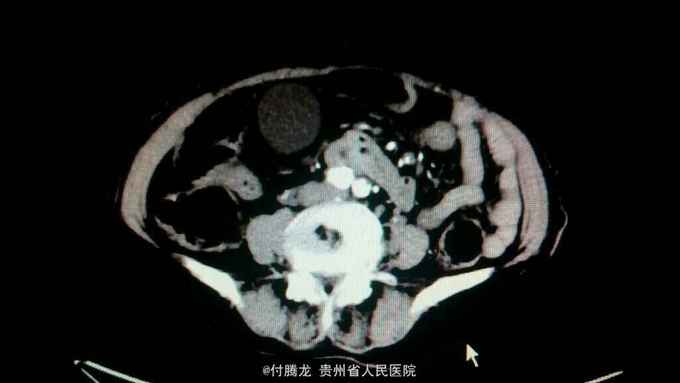

全身黄染伴乏力2月 病史:患者2月前无明显诱因下出现乏力,无恶心呕吐,畏寒发热等,后逐渐发现全身皮肤黄染。遂至当地医院检查。腹部ct提示胆总管下段狭窄,不排除炎性狭窄。胆红素200+。为进一步治疗来我院。

查体:全身皮肤及巩膜重度黄染,上腹轻压痛。 辅助检查:胆红素234,直接胆红素106,间接胆红素128。ALT60,AST88。肿瘤指标199及AFP正常。腹部ct提示胆总管肠内段高密度结节,不排除结石。超声內镜提示胆总管下段梗阻,考虑壶腹部肿瘤。MRCP提示十二指肠壁内段梗阻。

诊断:梗阻性黄疸(壶腹部占位)。 处理:予内科保守治疗,因不明确肿物性质,向患者家属交代病情,如需明确需要行胰十二指肠切除。家属考虑患者年纪大,不同意手术。

患者治疗一周,复查胆红素149,ALT63。一般情况可, 讨论:胆总管下段梗阻,检查提示十二指肠壁内段占位,但患者199正常,如需明确诊断,需行whipple手术。但手术创伤相对大。若不行手术,如为恶性,担心错过手术机会。